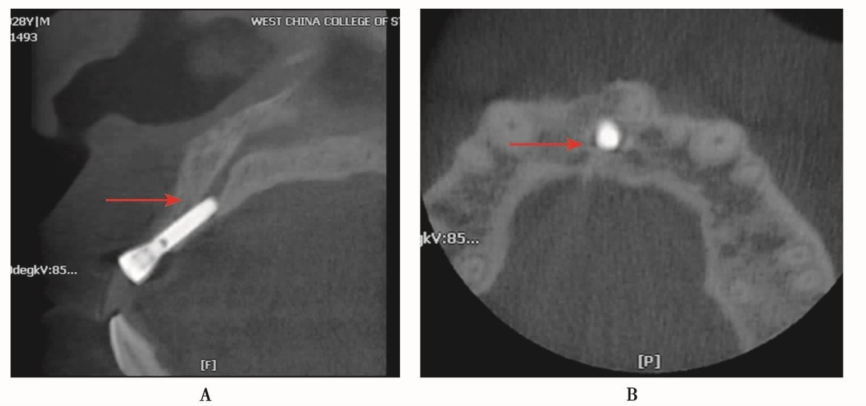

在上颌前牙区最重要的一个结构就是鼻腭管,是鼻腭神经和血管通过的地方,全景片和牙片又不能很好地显示该结构。鼻腭管的大小是不一致的,有的可以很粗大而且不规则。在临床有时候可以看见种植体进入鼻腭管的现象,有的轻度压迫鼻腭管(图4),有的部分或者大部分进入鼻腭管(图5、图6)。尽管种植体进入鼻腭管不会像损伤下牙槽神经管出现非常明显的症状,但在临床工作中还是要尽量避免损伤鼻腭管。术前CBCT的检查及判断就显得十分重要。

图4 种植体部分进入鼻腭管,压迫鼻腭管A.矢状位显示种植体部分进入鼻腭管;B.水平位显示种植体近中压迫鼻腭管

图5 种植体进入鼻腭管,压迫鼻腭管A.矢状位;B.水平位

图6 矢状位显示种植体进入鼻腭管,种植体大部分完全位于鼻腭管内